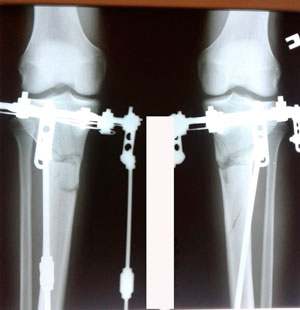

Исходник - 21 год. Бишкек.

Дата операции 30.06.2020

перед крутками

Вложения